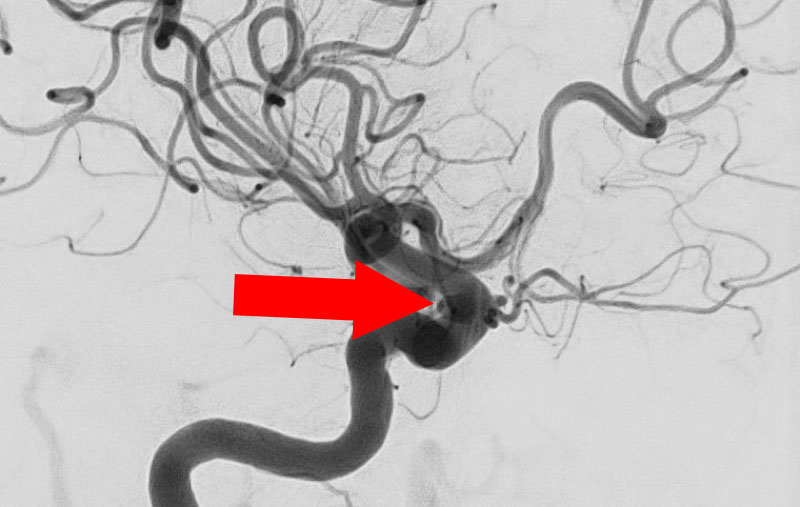

No.1617 手術前